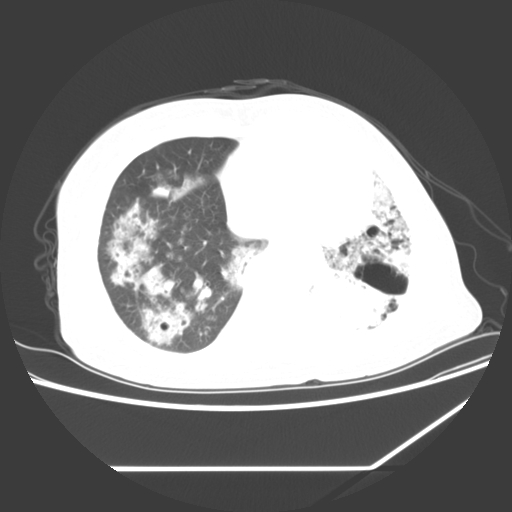

标题: CT25393:病人45岁,咳嗽,吐黄痰带血丝,发热,胸闷月余 [打印本页]

标题: CT25393:病人45岁,咳嗽,吐黄痰带血丝,发热,胸闷月余

1、左肺中央型肺癌并双肺弥漫性转移   2、双肺部感染    3、肺大泡     4、左侧胸腔积液

双侧肺弥漫性病变,可见“空泡征”及“蜂窝征”,考虑肺泡癌可能性大,左侧胸腔积液,考虑胸膜受累可能!

考虑肺泡癌,建议排除感染。

考虑肺泡癌

1)不排除肺泡癌可能。2)左侧胸腔积液。